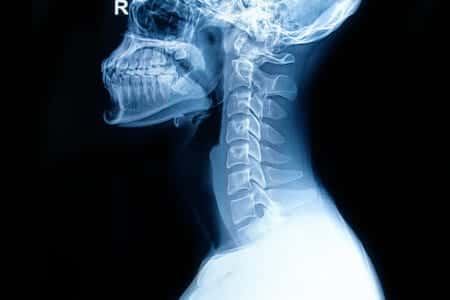

This case involves a young female who was involved in a significant accident in which she rolled her SUV while traveling down the highway. After the accident, she was transported to the emergency room where imaging studies were performed. The images that were taken weren’t conclusive of a cervical fracture, and the woman was discharged within the day. During her time in the hospital, she complained of severe back pain, however she was able to walk with assistance. As was later determined, the woman had sustained a serious cervical fracture which went undiagnosed. Within hours of being discharged, the patient developed permanent paralysis. It is alleged that the ER physicians failed to provide a thorough and adequate workup, such as ordering additional imaging studies, or conducting testing to ensure no cervical fracture or major injury was present, which resulted in the loss of the opportunity for neurosurgical intervention. It was also alleged that timely neurosurgical intervention for this patient would have prevented the patient’s paralysis.